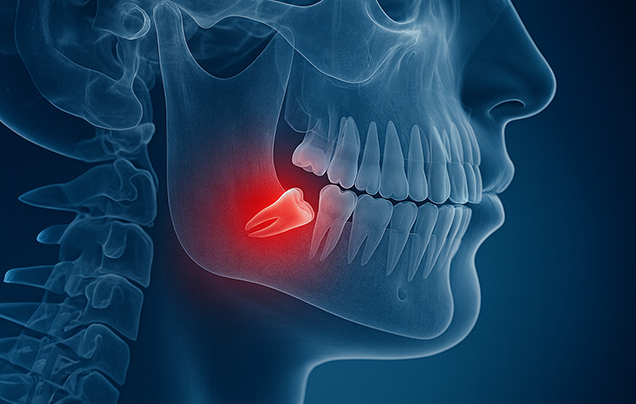

- 사랑니 발치

- 안전한 시술이 가장 중요합니다.

사랑니가 정상적으로 나지 않거나, 염증 통증 충치 등

문제를 일으킬 때 발치가 필요합니다.

사랑니의 위치에 따라 신경, 상악동 등 중요한 부분과 근접하고 있고

이를 피해 안전하게 발치하는 것이 중요합니다.

저희 병원에서는 3차원 CT 영상으로 술전에 충분히 진단하고 분석하여

안전하게 사랑니를 발치합니다.